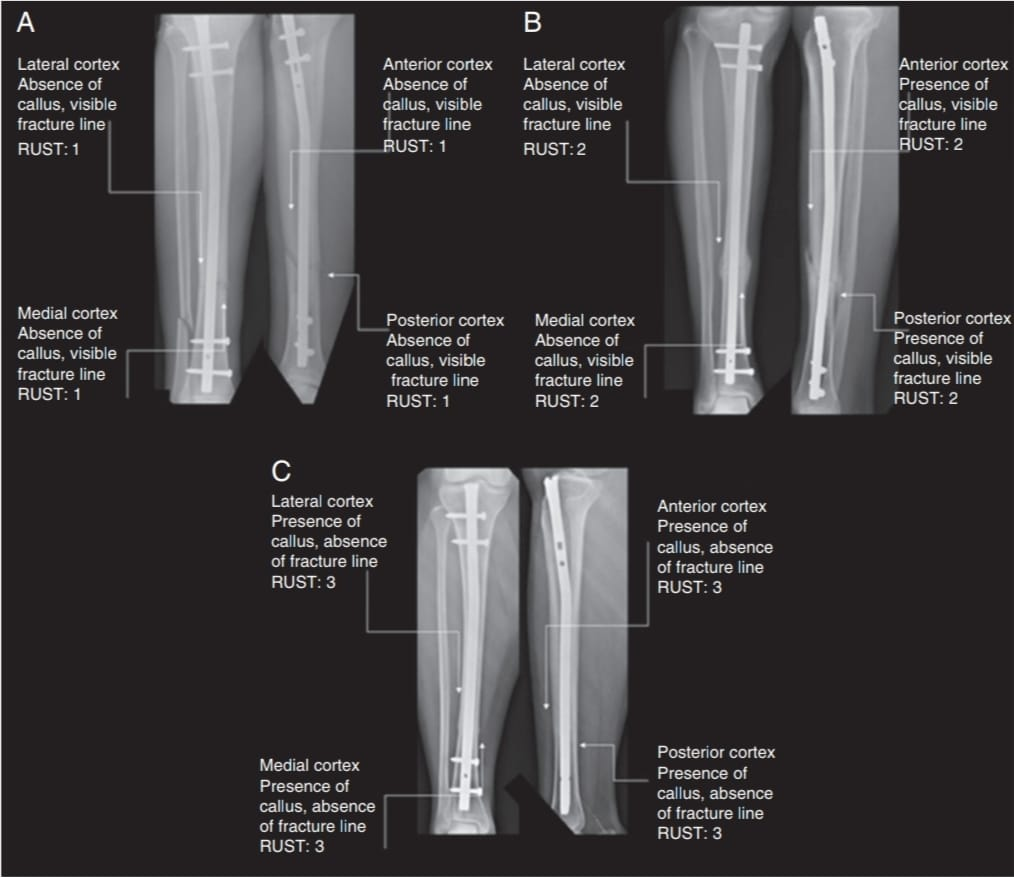

First, coronal plane malalignment was studied during the immediate and 6th month post-operative period (last follow-up) by measuring Lateral Distal Tibial Angle (LDTA) (Normal LDTA = 89° (86°–92°) and the inference was to rule out varus/valgus >5° change. Then sagittal plane malalignment during the immediate and 6th month post- operative period by measuring Anterior Distal Tibial Angle (ADTA) (Normal ADTA = 80° (78°–82°) and inference was to rule out procurvatum/recurvatum >10° change. Radiographic Union Score for Tibial fractures (RUST) scoring was used to assess fracture healing status and to find any delay in healing (delayed union/non- union) based on callus formation and presence of fracture line

(RUST score = sum of all four cortex scores with a total score of 4–12).

*Note: Using AP and lateral radiographs, the radiographic evidence of healing on at least three cortices was used to determine fracture union. The absence of radiographic signs of bone union and pain at the fracture site during weight-bearing after the 6th month following surgery were considered as indicator of non-union. Fig. 2 describes the overview of the RUST score [6]. Fig. 3 describes RUST score in three phases of consolidation [7].

Figure 2: Overview of the radiographic union score for tibial fractures score [6].

Figure 3: Radiographic union score for tibial fractures score in three phases of consolidation [7] (A=4, B=8, C=12).